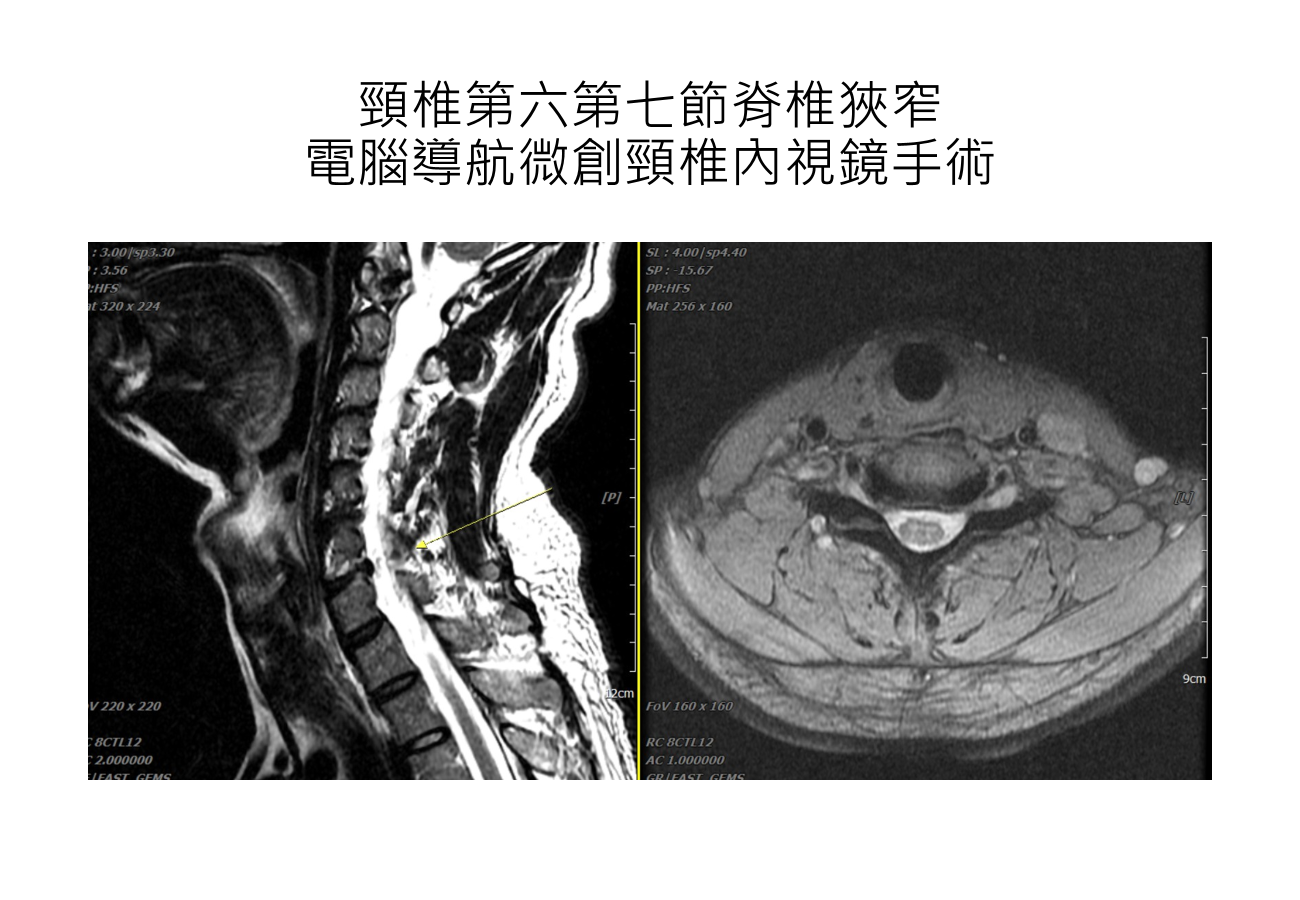

放大64倍顯微技術:頸椎內視鏡手術

頸椎內視鏡手術,在術中會利用內視鏡器械,從頸部後側或前側進入,進行局部椎板或椎間盤的微創切除與神經減壓等處理。